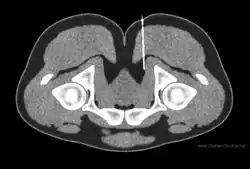

Diagnostic nerve blocks are very effective for identifying sensory entrapment points. Their strength is that they can directly measure whether a given nerve is contributing pain, or not. They are precise and reproducible.[36] As successful blocks require accurate targeting of the nerve, this is done under image guidance such as fluoroscopy, ultrasound,[37] CT,[37] or MRI.[38] Ultrasound is popular choice because of its soft-tissue contrast, portability, lack of radiation, and low cost, but is not good at depicting deeper structures like the deep pelvic nerves. For deeper structures, CT and MRI are more appropriate, although the equipment is more expensive.[39][40][41][37][38]

Imaging studies

MR and ultrasound can be used for peripheral nerve imaging.[46] Ultrasound is common for superficial nerves of the upper extremity such as carpal tunnel syndrome.[47] MR imaging is not always reliable in that often the clinical assessment and imaging do not match for peripheral neuropathies.[48] That is, there are false positives and false negatives which bring into question how reliable these scans are for diagnosis and surgical planning. There are known limitations of MR for the identification of nerve entrapment: